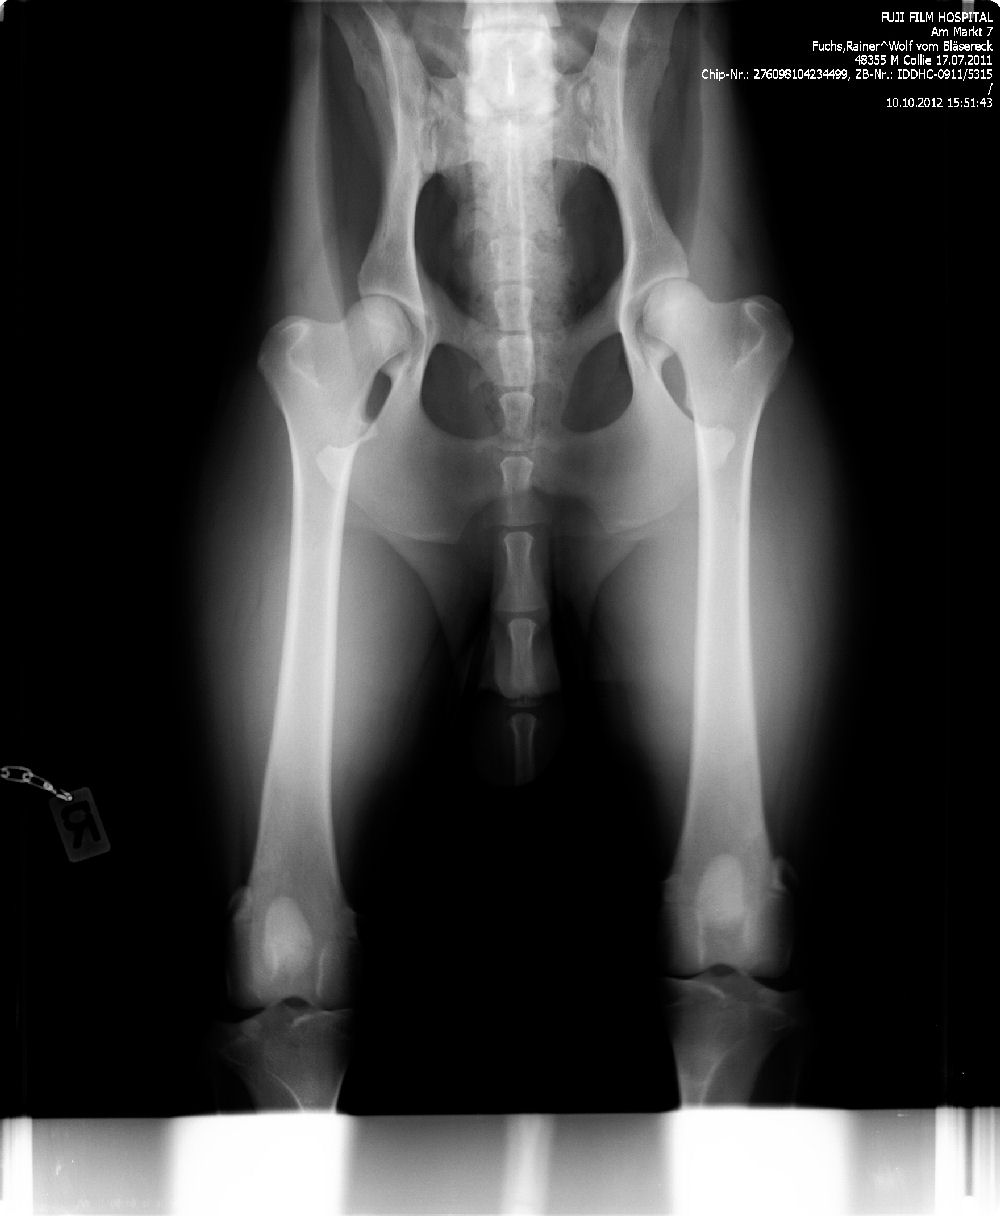

Ab dem Jahr 2008 wird nur noch Digitales Röntgen durchgeführt, da wir auch hier wieder führend und transparent sind, zeigen wir gern die Röntgenbilder ! Bei Züchtern, die dies nicht tun, haben Sie weniger Sicherheit !